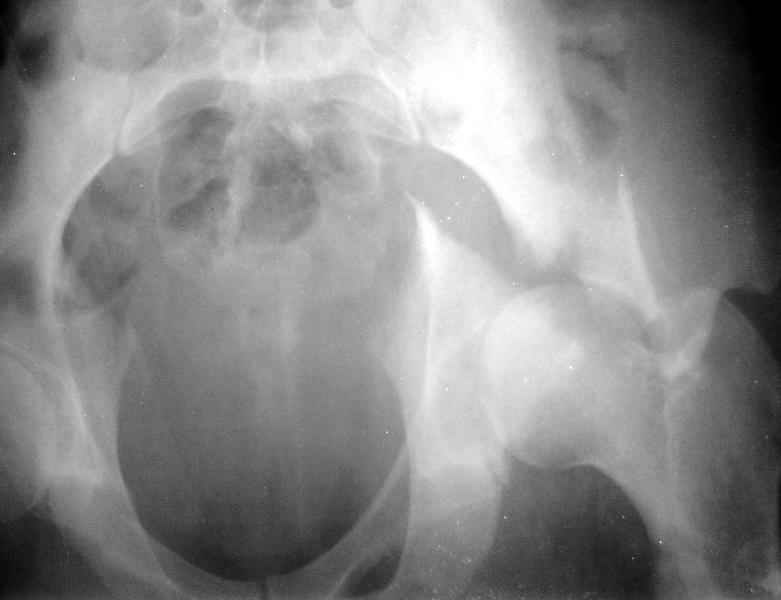

Сегодня на приеме был пациент, чьи начальный снимок напомнил обсуждаемый сейчас (см. выше). Снимки в других проекциях, показывающие истинный характер повреждения, ниже. Это inlet проекция (вход в таз) и запирательная проекция Judet.

1

2